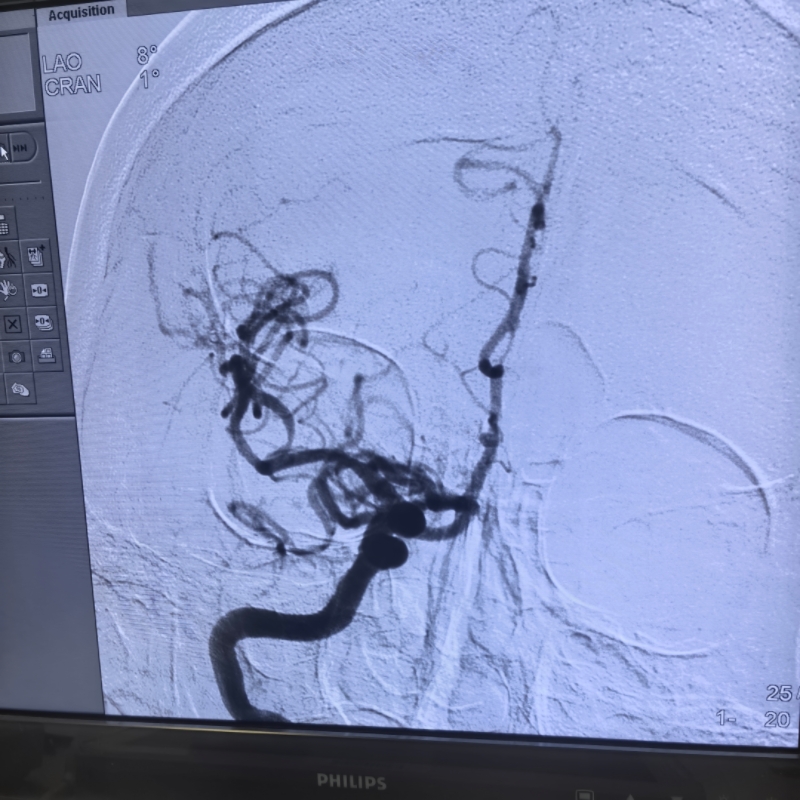

“患者神志不清、肢体瘫痪,核心病因是脑血管闭塞,若不及时取栓,脑细胞会持续坏死,不仅可能终身残疾,还会因病情进展危及生命。躺不平、做不了 CTA 都不是放弃的理由,我们得想办法创造治疗条件!” 神经介入团队傅新民主任、宗海亮主任、陈施吾医生当机立断。他们没有囿于常规检查流程的教条,而是基于指南原则与患者危重症情综合研判:跳过 CTA 直接行数字减影血管造影(DSA),在造影确认大血管闭塞后立即实施取栓,以最直接的方式为抢救争取宝贵时间;同时迅速制定心功能改善方案,在导管室张学萍护士长、朱护师的配合下立即泵入硝酸甘油减轻心脏后负荷,联用利尿剂降低前负荷,双管齐下改善心功能。令人振奋的是,用药后不久,患者的气喘、胸闷症状逐渐缓解,竟然能够平稳平卧 —— 这为取栓治疗打开了关键突破口。

时间就是大脑,每一秒都关乎神经功能的恢复。神经介入团队争分夺秒,快速完成穿刺、造影、取栓一系列操作,全程仅用 1 小时便成功开通闭塞血管。术后,患者顺利转入 ICU 监护,而今天一早,奇迹已然发生:张大妈完全清醒,左侧肢体活动能力明显好转,从生死边缘被成功拉回。